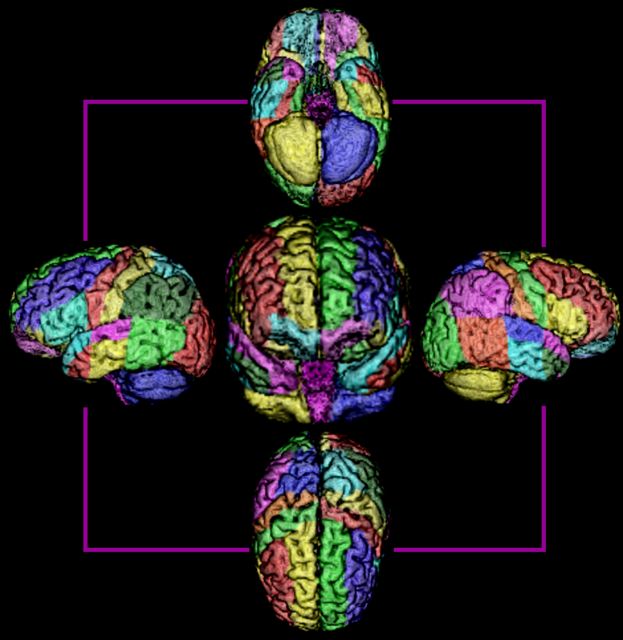

.jpg) Το logo του ALBERT, σχηματισμένο από χαρτογραφημένους νεογνικούς εγκεφάλους

Το logo του ALBERT, σχηματισμένο από χαρτογραφημένους νεογνικούς εγκεφάλους Η ευαισθησία του έλληνα επιστήμονα, η οποία αποτυπώνεται στο ίδιο το όνομα της μοναδικής παγκοσμίως πλατφόρμας που ανέπτυξε –καθώς και σε άλλες εκφάνσεις του αφού μαζί με την οικογένειά του χρηματοδοτούν αναπτυξιακά έργα στην Αιθιοπία –προέρχεται από την ίδια τη ζωή του. Το ALBERT (το οποίο επιστημονικώς αποτελεί την ακροστοιχίδα του A Label Based Encephalic Regions of interest Template) είναι ουσιαστικά αφιερωμένο στον μικρότερο αδελφό του Αλβέρτο ο οποίος γεννήθηκε πρόωρα και λόγω ιατρικού λάθους ζει με νοητική υστέρηση. Ετσι ο κ. Γούσιας βάλθηκε να βοηθήσει στα χρόνια που έρχονται άλλες οικογένειες –όσες βιώνουν τη γέννηση πρόωρων βρεφών και όχι μόνο –ώστε να μπορούν να βλέπουν από νωρίς τυχόν προβλήματα που θα «γεννήσει» ο εγκέφαλος των παιδιών τους.